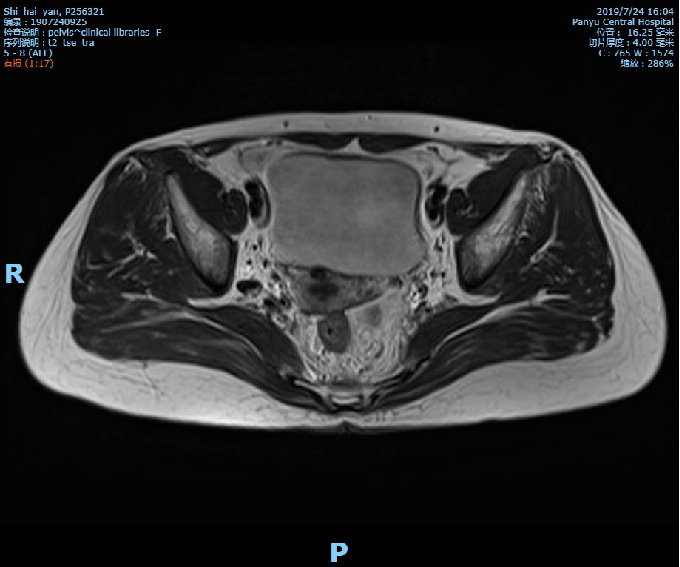

2019-10-09复查盆腔MR示直肠全段管壁不均匀增厚,以中段较明显,最厚处约11mm,较前相仿,仍考虑直肠癌累及浆膜面,较前略有好转,不除外直肠前筋膜受累;胸腹CT未见转移征象。

术前影像学检查: